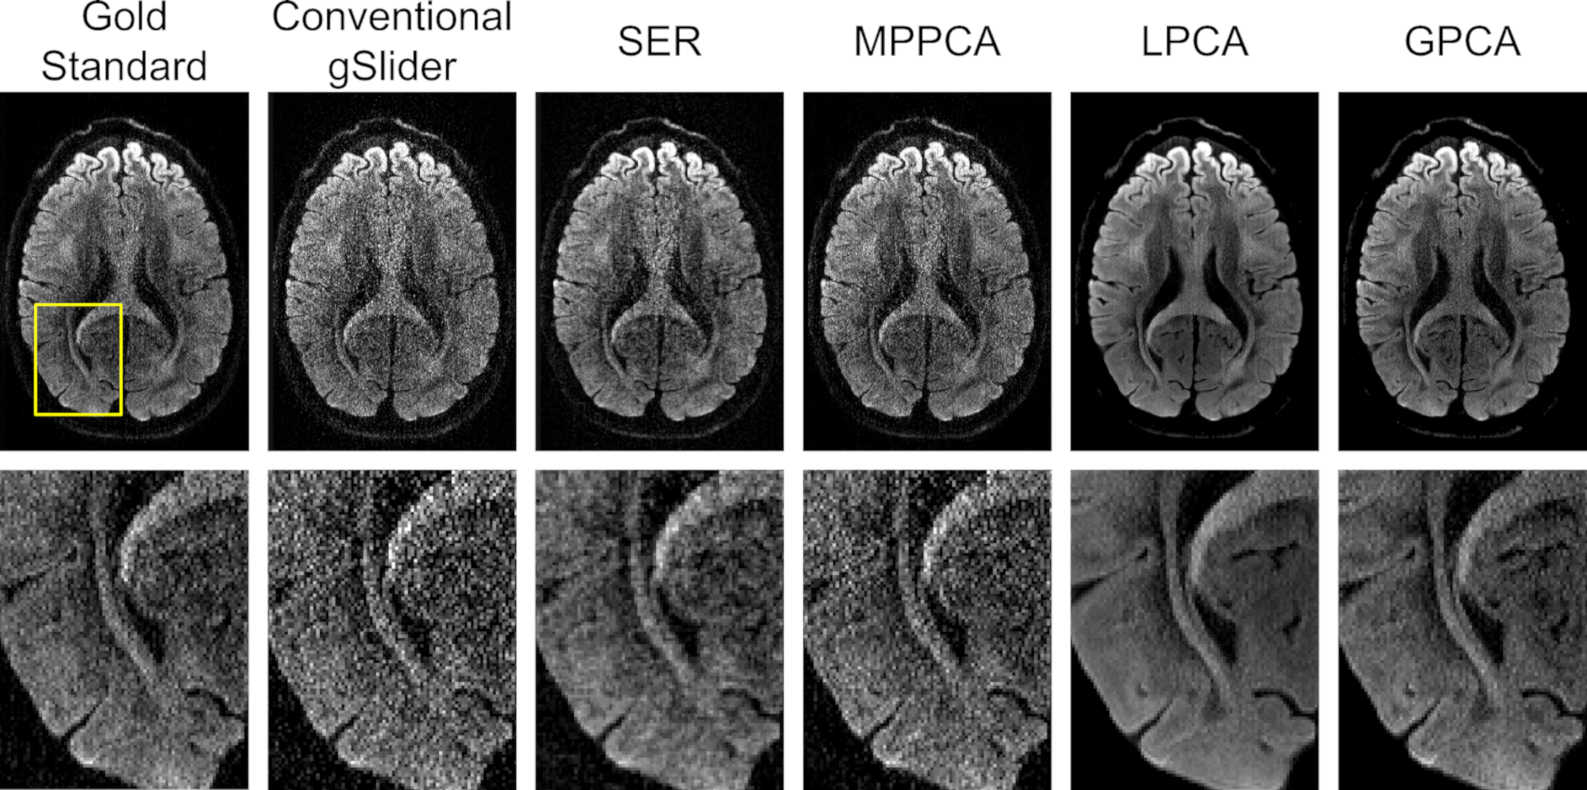

More detail is available from inspecting the zoomed-in images presented in Fig.Β 3, which also includes comparisons against MPPCA, LPCA, and GPCA. From this figure, it can be observed that all four denoising approaches have an apparent reduction in noise, although the extent of this varies from method to method. MPPCA appears to have the least amount of noise reduction among the four, while both GPCA and LPCA produce very crisp-looking images with minimal obvious noise content. We would argue that the SER result does not look as crisp or cosmetically pleasing as the LPCA and GPCA results, although still represents an improvement over MPPCA.

Looking at the NRMSE values for the DWIs, which are shown in TableΒ 1, we observe that LPCA has the smallest NRMSE, followed by SER, GPCA, and MPPCA. The good performance of LPCA in this case is not surprising, since its parameters were tuned using perfect knowledge of the gold standard to optimize this NRMSE value, and because LPCA has more flexibility than GPCA to adapt to the different properties of different image regions. On the other hand, it may be surprising that the SER result has smaller NRMSE than the GPCA result, given that the GPCA result was also designed to minimize this NRMSE value based on perfect prior knowledge that was not available to SER. This suggests that even in the ideal case, while global low-rank modeling can offer some degree of improvement, this model may be intrinsically more limited than some of these other approaches in this type of application. Interestingly, there is a major performance difference between LPCA and MPPCA, even though both of these results are based on the same underlying locally low-rank data model. This result illustrates the importance of choosing good rank parameters, although it should be noted that MPPCA uses a conservative automatic rank-selection rule that is not necessarily designed to achieve optimal NRMSE.

Figure 3: Comparison of a slice from a representative DWI obtained by different reconstruction and denoising approaches. Zoomed-in images (from the region corresponding to the yellow box shown in the gold standard image) are also shown for easier visualization of fine image details.